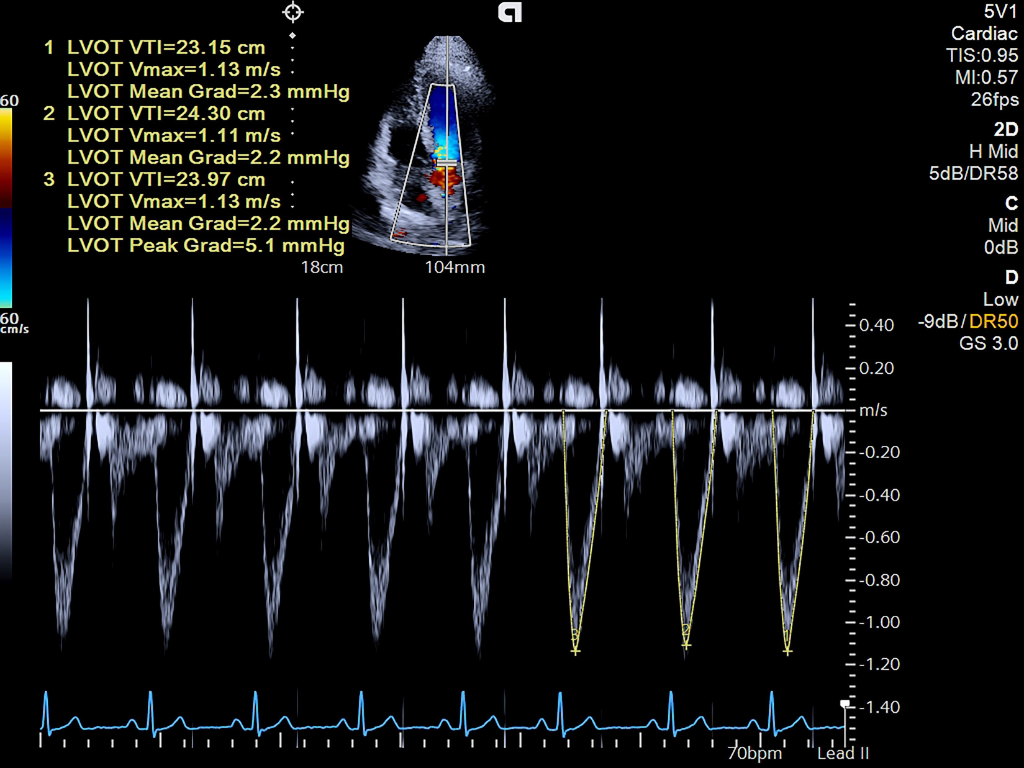

- 4D HeartAI utilizes proprietary AI to process complex cardiac data, 4D analysis, and imaging for TTE and TEE for timely and accurate decision making.

- AI Assist alleviates time consuming echo calculations and standardize exams across users.